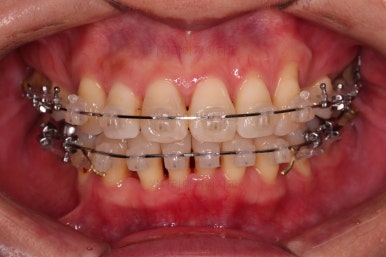

동래임플란트교정 초진 시 입안의 모습입니다.

치열이 전반적으로 삐뚤어져 있는 양상이고요.

아랫니가 윗니보다 더 많이 삐뚤어 있는데요.

장치를 부착했습니다.

이번 환자분이 선택한 장치는 데이몬 클리어라고 하는 현존하는 자가결찰 세라믹 장치 중에 가장 심미적인 장치입니다.

사실상 멀리서 보면 철사를 제외하고는 거의 눈에 띄지 않는 모습인데요.

단점은 부피가 다른 장치들보다 약간은 더 크기 때문에 입이 약간 더 나와보일 수 있다는 점이죠.